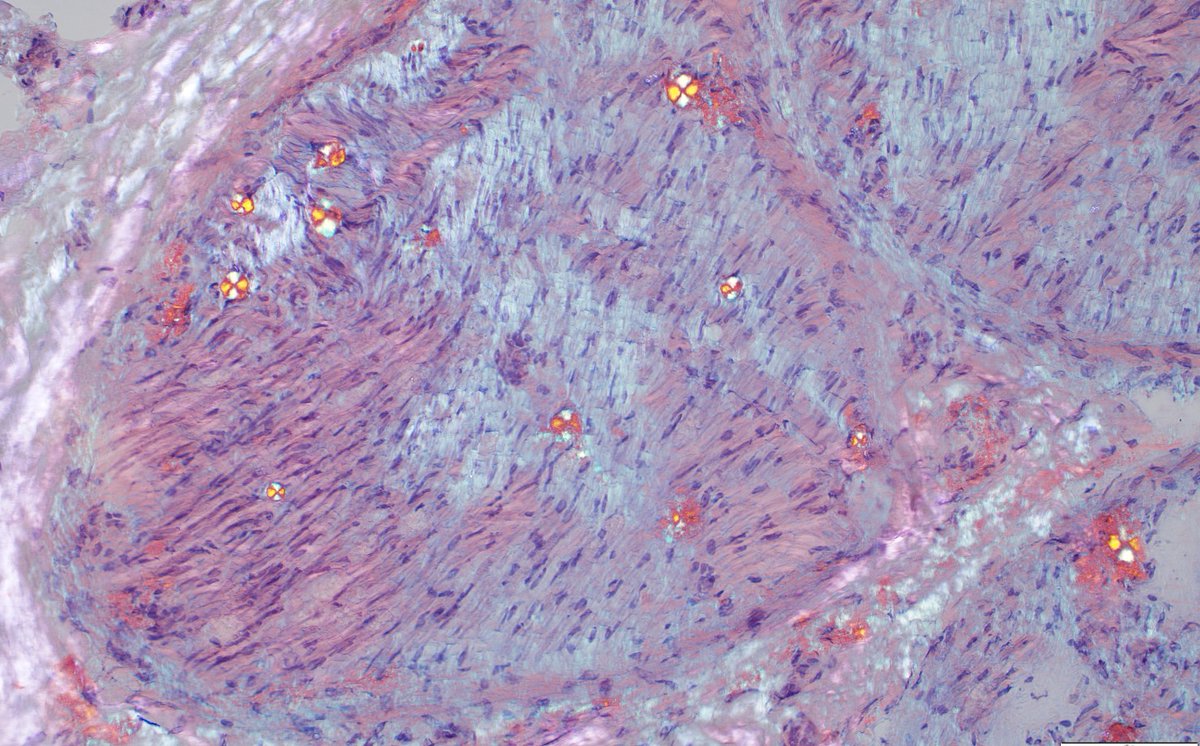

The Phase III CARES trial of #anselamimab in #ALAmyloidosis did not meet its primary endpoint, but showed clinically meaningful benefit in a predefined high-risk subgroup. More details to follow at upcoming meetings. @BU_Amyloidosis astrazeneca.com/media-centre/p…